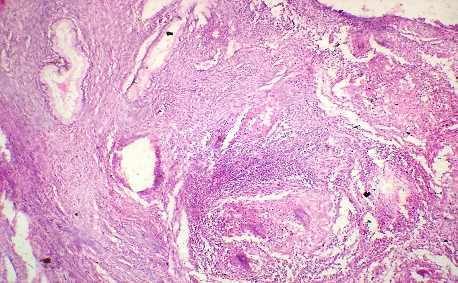

HISTOPATHOLOGY

Ultrasonically guided fine needle aspiration cytology of a mass in front of the neck of a 40 year old female. Patient complained of severe back ache and had osteoporosis. Fig 1 and Fig 2 : are shown. Make your diagnosis.

Fig 1

Fig 2